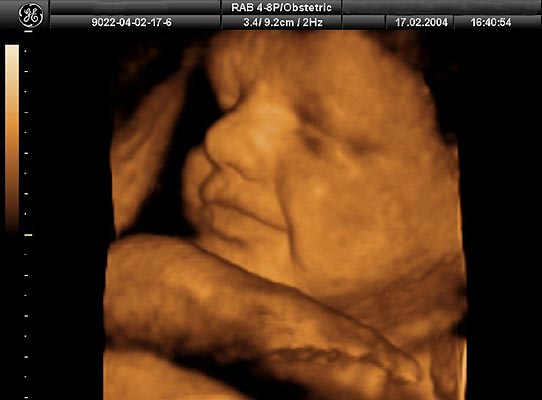

Tercer mes y primer susto. Se trata de una recreación por ordenador realizada a partir de ecografías reales en 3D y 4D.